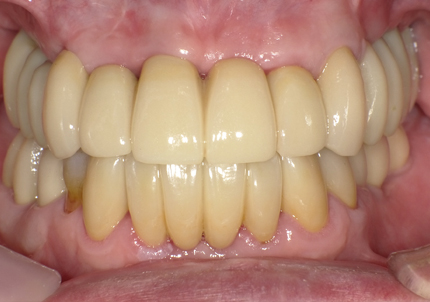

22.最終補綴物完成・装着口腔内写真(2021年1月)

23.自然な形態のインプラント歯頚部

適切な治療計画と治療技術を有することで、このような自然な形態のインプラント歯頚部を形成することができます。

24.口腔内写真

【 2018年 術前 】

【 2025年5月 現在 】